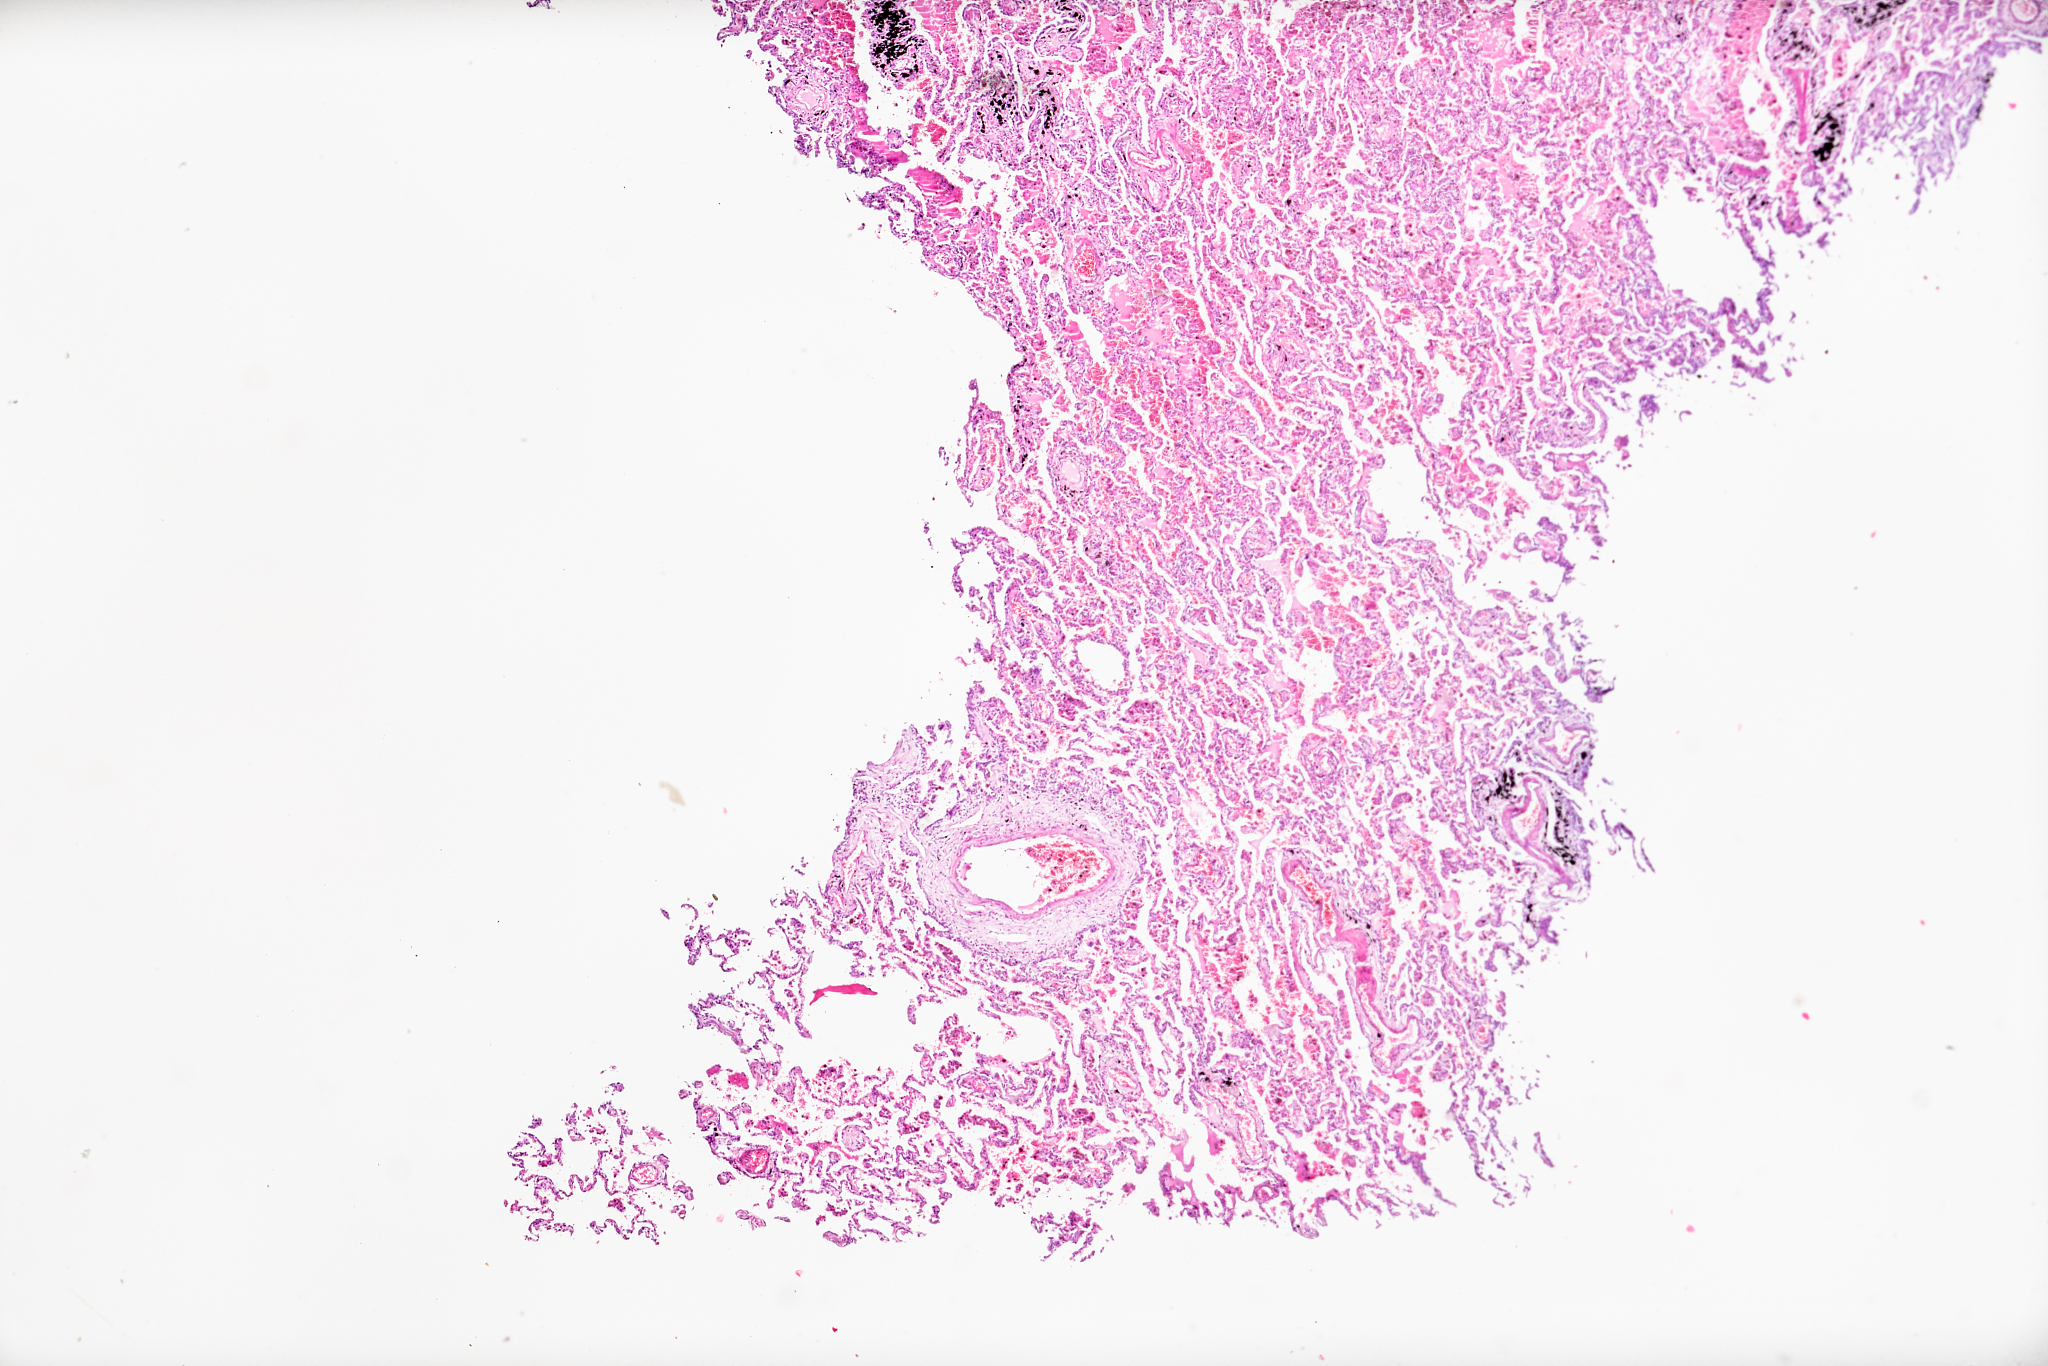

患者大叶性肺炎首选考虑药物

治疗大叶性肺炎的首选药物是抗生素。常用的抗生素包括青霉素、头孢菌素、氨基糖苷类药物等。选择药物应根据患者的病情、病原体种类及药物敏感性等因素综合考虑。在使用抗生素的过程中,应严格按照医生的建议和处方用药,不要随意更改剂量或停药,以免影响疗效。同时,应注意加强营养和休息,增强身体免疫力,有助于加速康复。